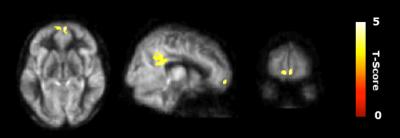

The 19 participants in the cognitive reasoning training group (SMART) showed significant gains pre- to post-training in high-quality innovation performance, improving their performance by an average of 27 percent from baseline to mid- and post-training periods on innovative cognition measures. The physical exercise and control groups did not show improvement. These positive gains in the reasoning training group corresponded to increased connectivity among brain cells in the central executive network of the brain, an area responsible for innovative thinking.

"Advances in the field of MRI are allowing us to measure different aspects of brain function," said Dr. Sina Aslan, an imaging specialist at the Center for BrainHealth. "Through this research, we are able to see that higher activity in the central executive network corresponded to improved innovation. These findings suggest that staying mentally active not only mitigates cognitive decline, but also has the potential to restore creative thinking, which is typically lost with aging."